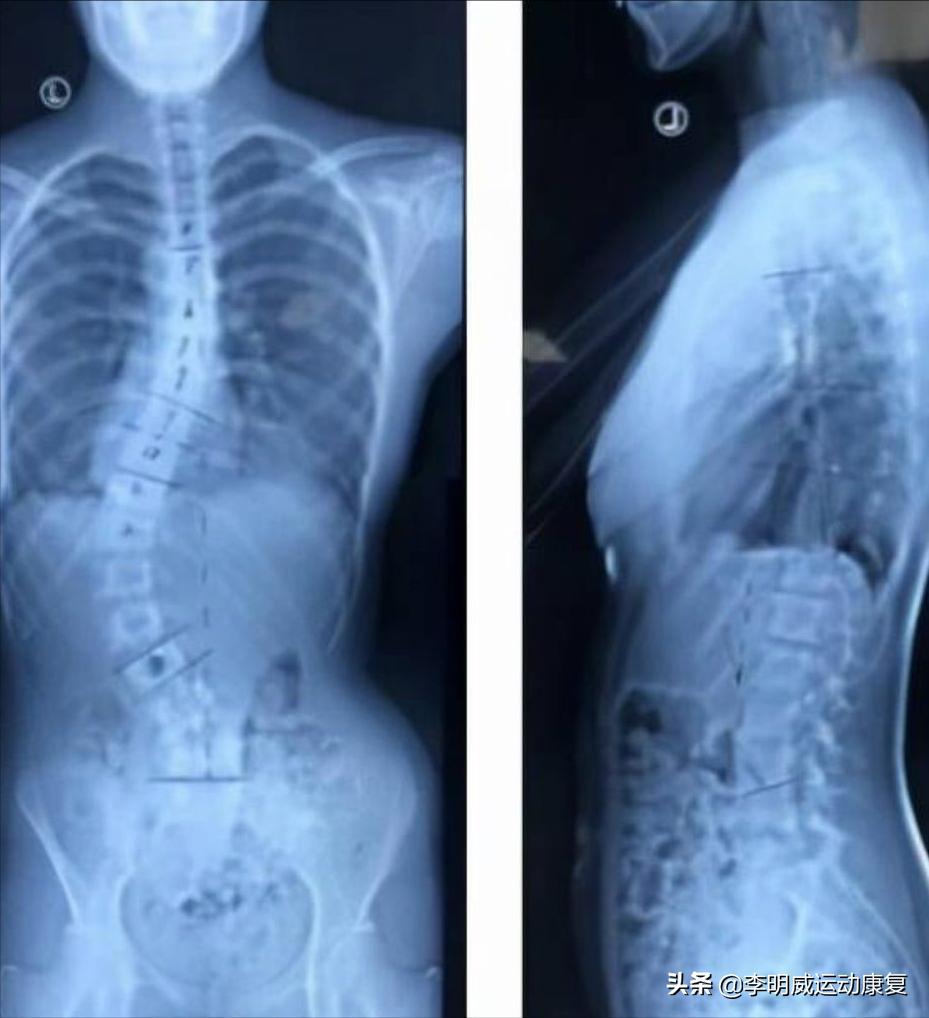

我给大家看一个脊柱侧弯的X光片,你可能会更加了解。

下面这个是很严重的,我看着都很心痛。